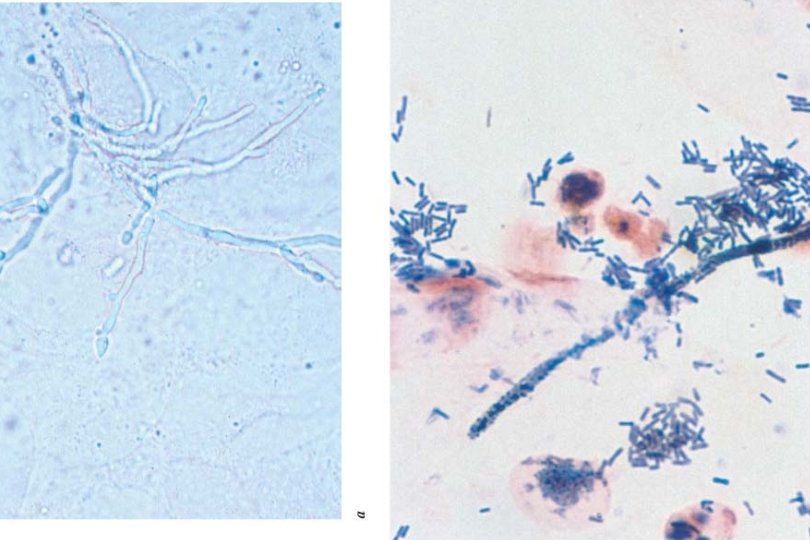

Diagnosis of VVC · · Clinical appearance and symptoms - Typically prominent irritative symptoms - Minimal discharge Laboratory - p. H <4. 5 - Negative amine odor - Microscopy (KOH preparation, Gram stain) - Isolation of Candida species usually not helpful • Nonspecific owing to asymptomatic carriage by most women some of the time and some women all of the time • C. albicans is normal vaginal flora